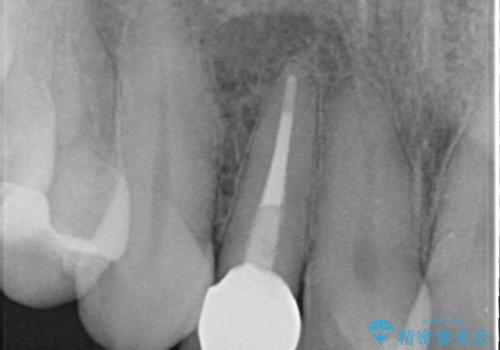

- 右上2番目の歯の変色が気になるといらっしゃった方の症例です。

再根管治療終了後、オールセラミッククラウンによる補綴を行いました。